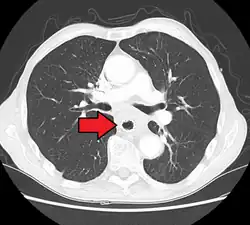

Additional testing is needed to assess how much the cancer has spread (see § Staging, below). Computed tomography (CT) of the chest, abdomen and pelvis can evaluate whether the cancer has spread to adjacent tissues or distant organs (especially liver and lymph nodes). The sensitivity of a CT scan is limited by its ability to detect masses (e.g. enlarged lymph nodes or involved organs) generally larger than 1 cm.[44][45] Positron emission tomography is also used to estimate the extent of the disease and is regarded as more precise than CT alone.[46] PET/MR as a novel modality has shown promising results in preoperative staging with fair feasibility and good correlation in comparison to PET/CT. It can enhance tissue differentiation with lowering the radiation dose to the patient.[47] Esophageal endoscopic ultrasound can provide staging information regarding the level of tumor invasion, and possible spread to regional lymph nodes.